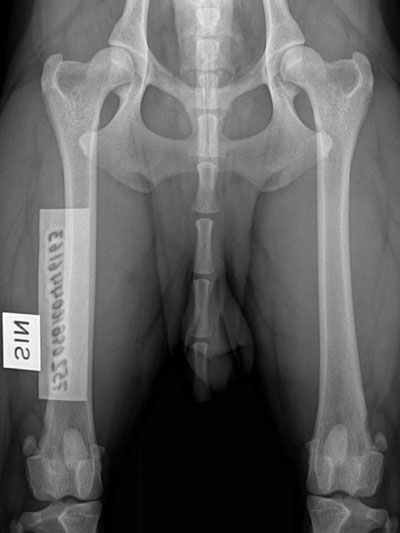

Fina B-höfter :)